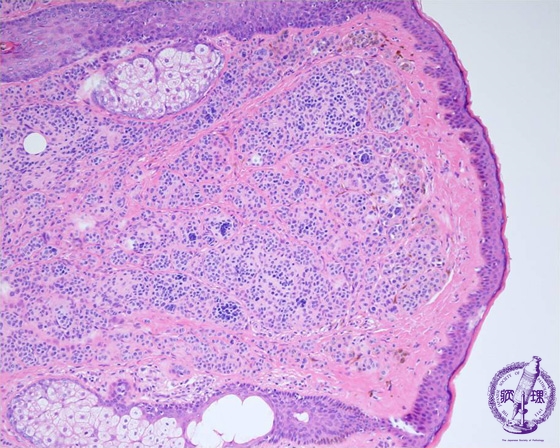

- (5)Melanocytic nevus (intradermal, junctional, compound)

Microscopic findings: Nevus cells scatter in the dermis (inside of a circle). Nevus cells are suggested to be induced by incomplete differentiation. They are related to the melanocytes and Schwann cells.